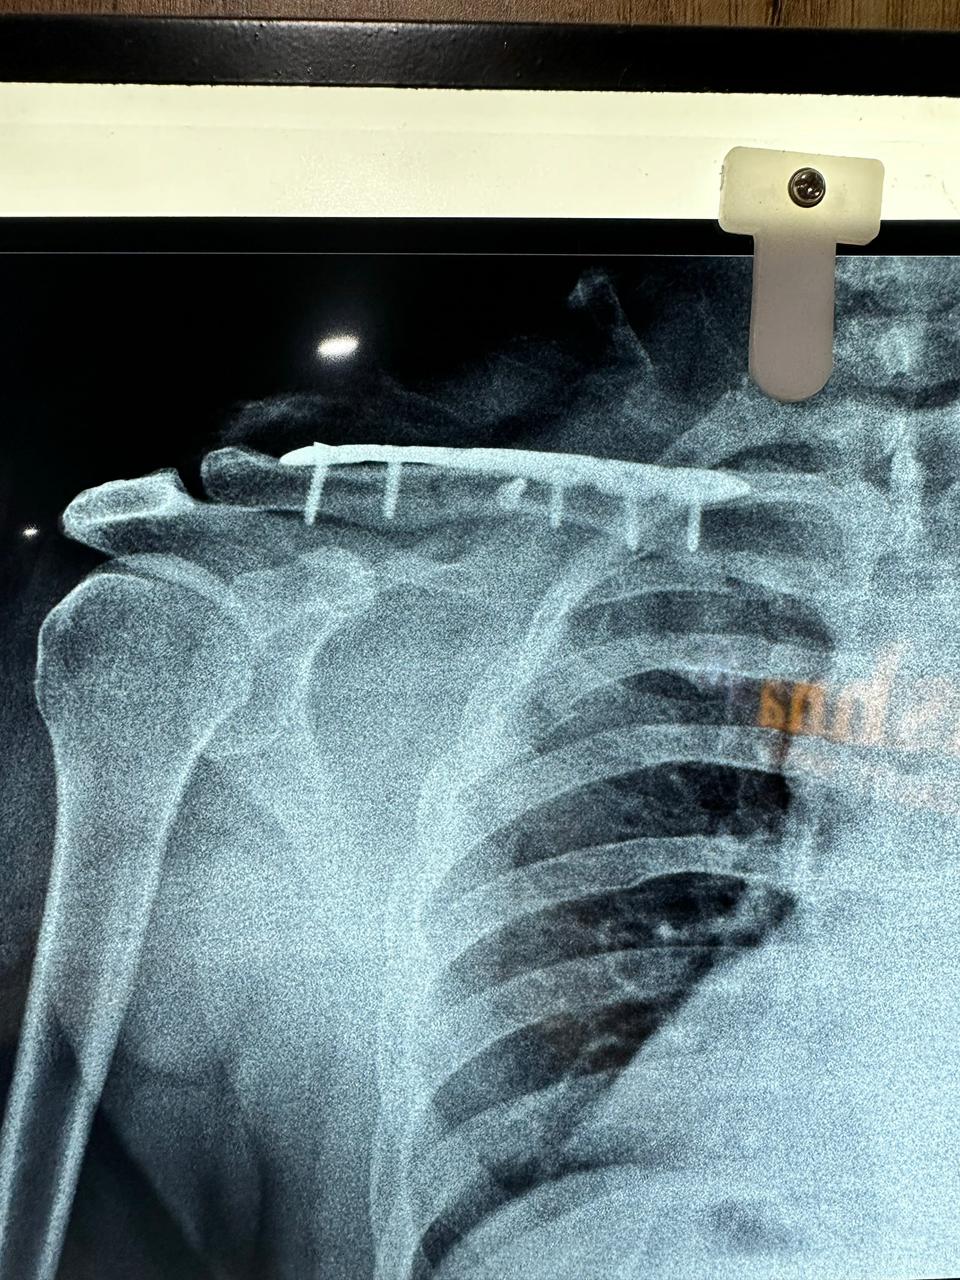

Moments That Mark Meaningful Recovery

Witness real patient transformations at The Ortho Clinic through images that reflect successful treatments and restored mobility.